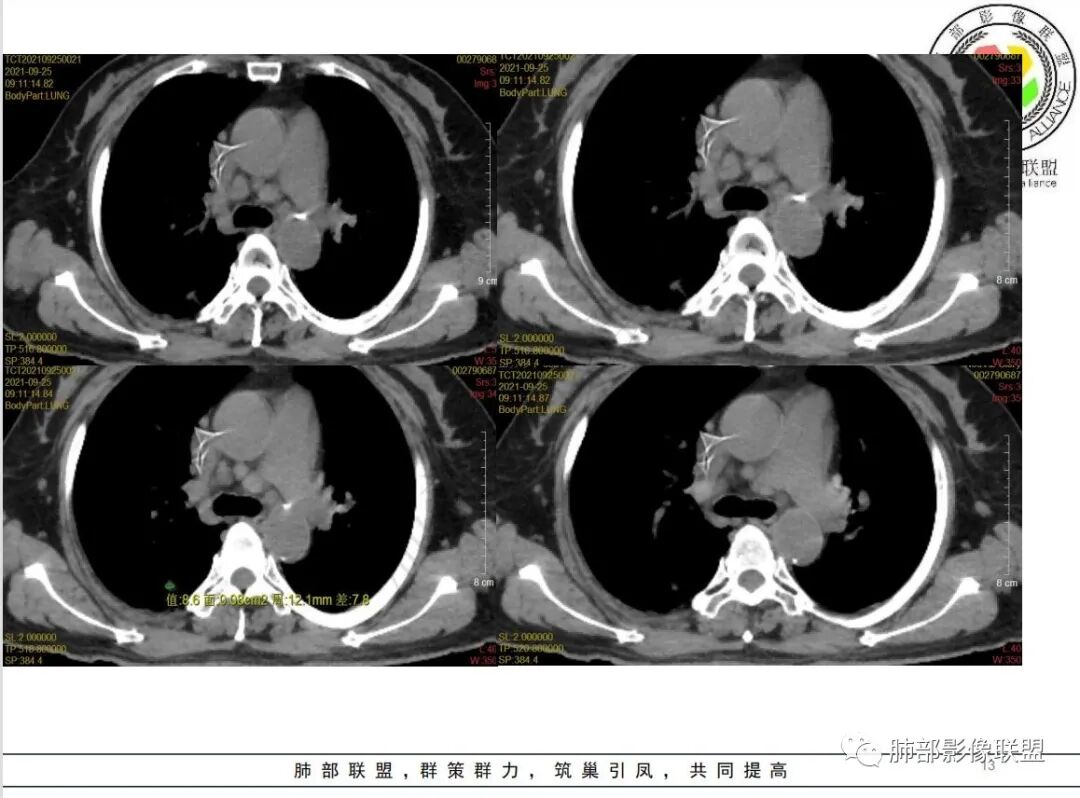

白血病化疗后,出现多发结节,边缘可见晕征,病灶内可见多发坏死,右肺中叶肺动脉可见充盈缺损,右肺中叶可见融冰征,考虑毛霉菌,右肺中叶肺动脉栓塞伴右肺中叶肺梗死。

有白血病病史,免疫妥协,双肺多发结节,纵隔增大淋巴结,短期抗炎治疗后复查,病灶明显增大,右肺门肿块,内可见坏死,临近肺动脉受侵,支气管闭塞,周围见阻塞性炎症,考虑感染性病变,毛霉菌可能大

4.白血病化疗后,CT上出现多发结节,边缘可见晕征,病灶内可见多发坏死,右肺中叶肺动脉可见充盈缺损,右肺中叶可见融冰征,右肺中叶肺动脉侵犯栓塞伴右肺中叶肺梗死,可符合真菌感染。

血管侵袭性曲霉病是最常见的类型,其特征是真菌菌丝侵入和阻塞中小肺动脉,形成凝固性坏死、肺泡出血或出血性梗死。

6.肺曲霉病典型的CT表现是结节周围有磨玻璃样的晕征表现,或胸膜为宽基底的楔形实变。晕征表现为曲菌感染的肺结节伴梗死和凝固性坏死,周围有肺泡出血。最终可出现空泡征象,并可观察到中央坏死组织与周围肺实质分离形成空气新月征。

晕征已被认为是侵袭性曲菌病的早期征象之一。